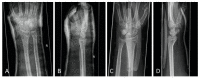

Although the benefits of hand orthoses were shown in previous studies, they have not been able to establish themselves in clinical routines. With a focus on patient satisfaction, this study aimed to evaluate the latest generation of hand orthoses after palmar plate osteosynthesis for isolated distal radius fractures in comparison with circular plaster casts. 50 patients (16% dropout rate) were randomly assigned to an orthotic group (immobilization by orthosis, OG) or a control group (immobilization by a plaster cast, CG). Intra-articular fractures were present in 74% of the cases, and unstable AO C3 fractures in 26%. Questionnaires on patient satisfaction, documentation of the time required, clinical scores (DASH, SF-36), range of motion, grip measurements and radiographs were used for evaluation. The OG proved to be equivalent to the plaster treatment in terms of patient satisfaction, and stability of the reduction, as well as clinical scores DASH and SF-36. The OG was even superior in terms of personal hygiene (p = 0.011), handling (p = 0.008) and better adaptability (p = 0.013). Significantly less time was required to apply the orthosis (p < 0.001). In addition to the good results achieved so far, the study showed that the latest generation of orthoses has several advantages over plaster cast therapy, and could therefore become established in everyday clinical practice.